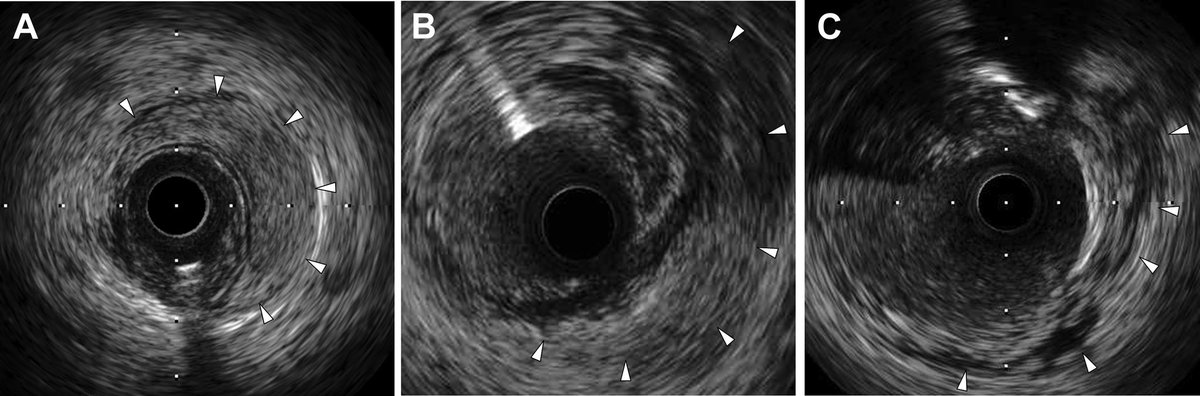

The Neo Lumen. Here is the IVUS 8 weeks after the initial modification. You can see the 3 channels: 1. TL remnant 2. Healed EP track 3. Partially healed dissection plane (location?) The combined areas greatly exceed that of the CTO!

Here is the IVUS - one of the more notable one. It shows the various types of healing that can take place after STAR. The two that haven’t been described are formation of a lotus root and TL regression with formation of a new(!) channel.

The formation of a double barrel ‘neo lumen’ HAS been described by @LAzzaliniMD et al. In fact, that is where I first learned that it is possible for the vessel wall to heal in this particular way. We have seen this in both CTOs and non-CTOs after CBA! From Lorenzo’s paper…